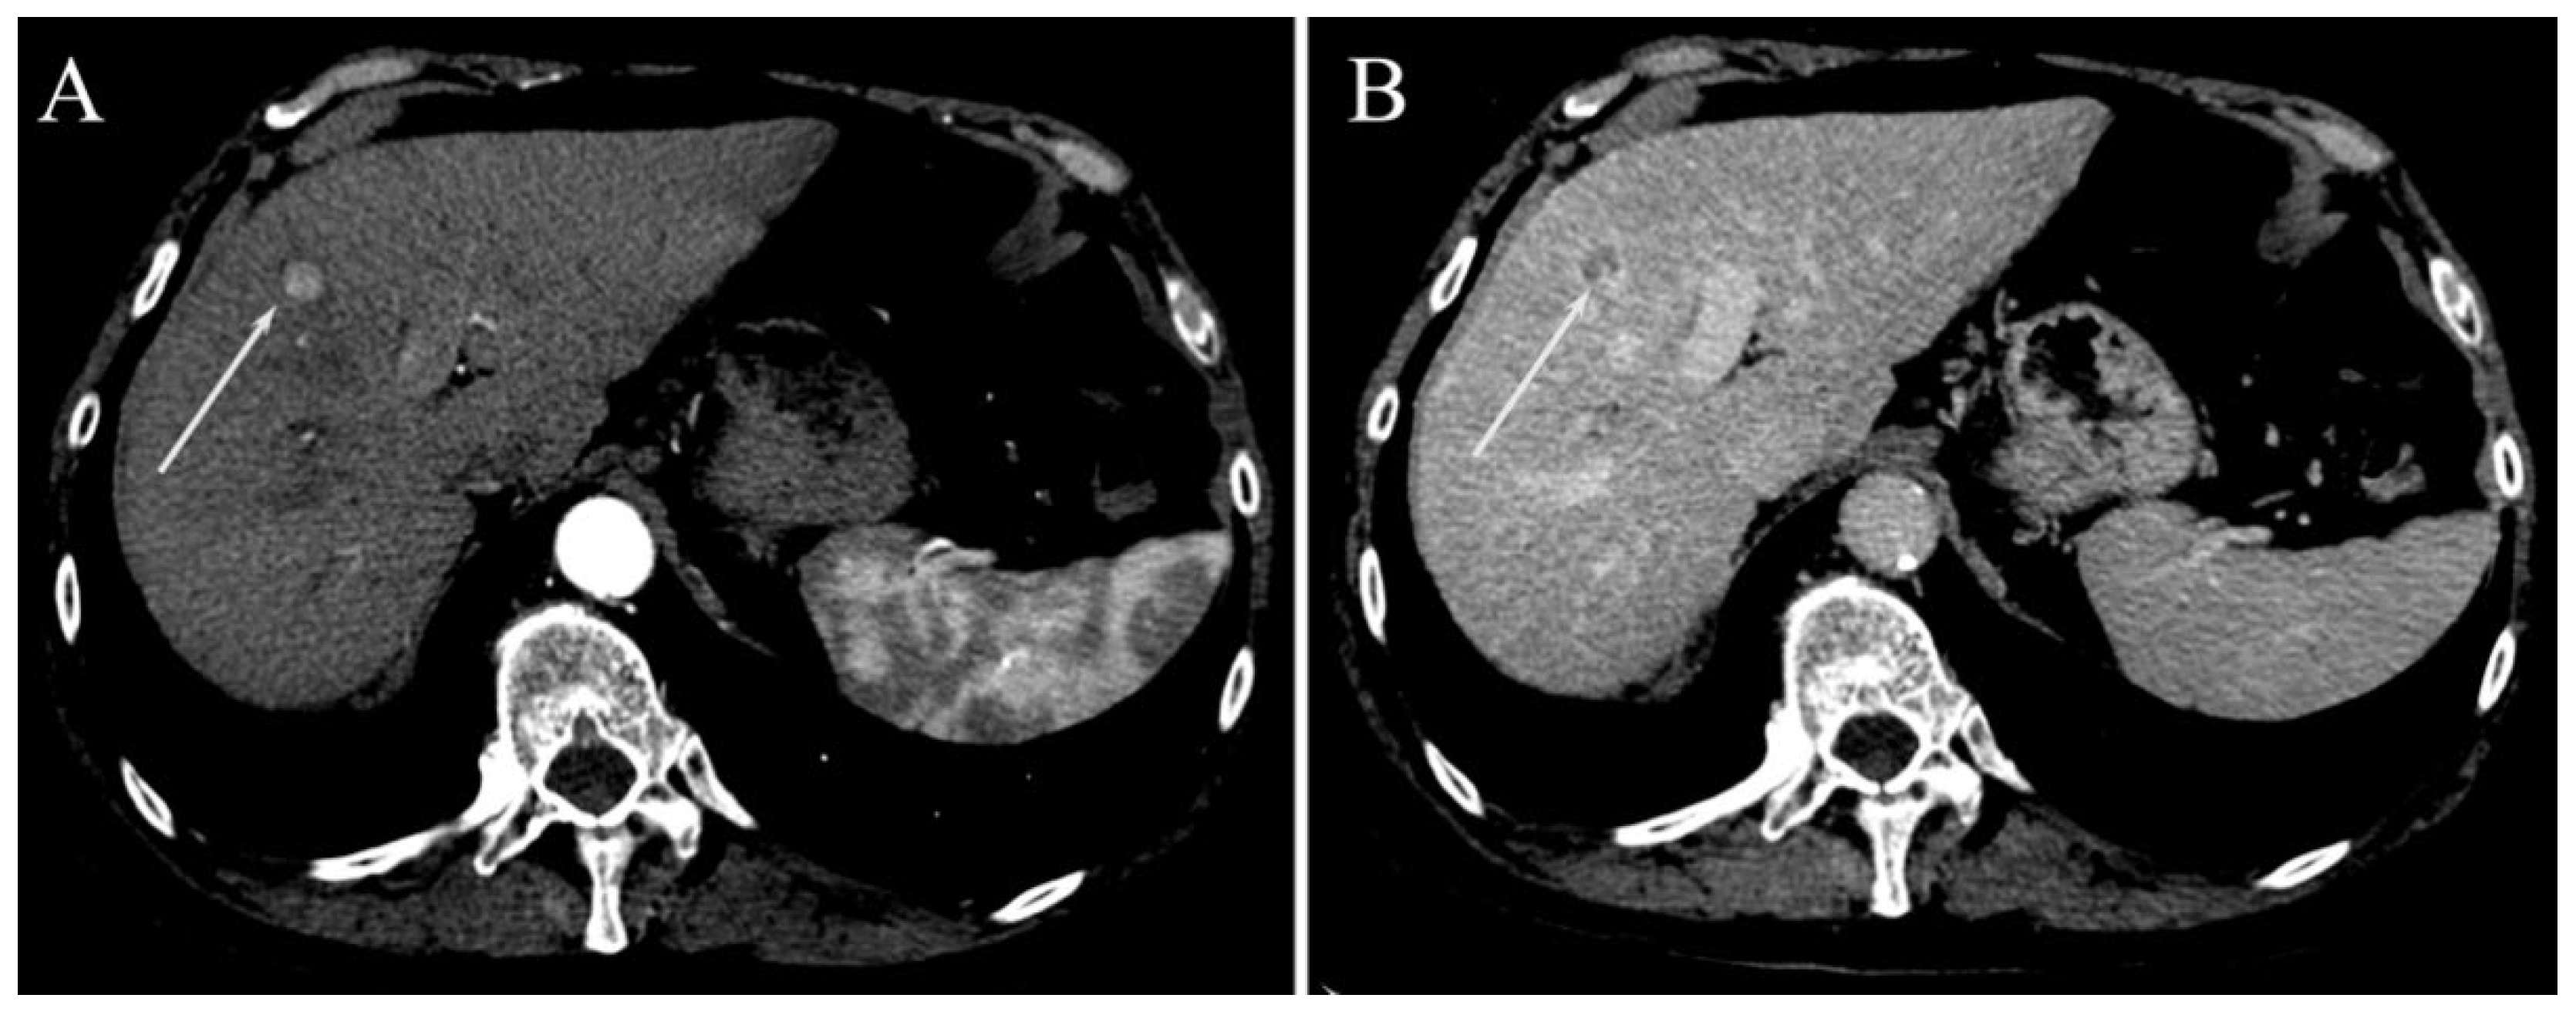

| Irregular margins | 21 (58.3%) | 26 (47.3%) | 0.391 |

| Peritumoral enhancement | 4 (11.1%) | 6 (10.9%) | 1.000 |